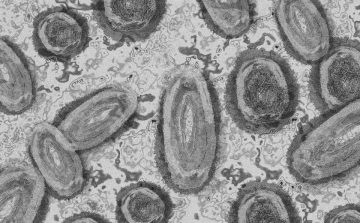

Tovább nőtt a majomhimlő-fertőzöttek száma Magyarországon

Újabb két embernél igazolt majomhimlő-fertőzést a Nemzeti Népegészségügyi Központ (NNK) a 33. héten - augusztus 15-től 21-ig -, ezzel 64-re nőtt a magyarországi esetek száma.

Meghaladta a 13 ezret a majomhimlő-fertőzöttek száma az Egyesült Államokban

Meghaladta a 13 ezret a majomhimlő-fertőzöttek száma az Egyesült Államokban, a legtöbb esetet Kaliforniában és New York államban regisztrálták.

Megfertőződött a majomhimlővel egy gyerek Németországban

Megfertőződött majomhimlővel egy négyéves kislány Németországban - jelentették kedden német hírportálok az országos közegészségügyi intézet (RKI) adatai alapján.

Tovább nőtt a majomhimlő-fertőzöttek száma Magyarországon

Újabb kilenc, 23-50 éves férfinél igazolták a majomhimlő-fertőzést Magyarországon, ezzel 42-re nőtt a fertőzöttek száma - közölte a Nemzeti Népegészségügyi Központ (NNK) csütörtökön az MTI-vel.

Tovább nőtt a majomhimlő magyar fertőzöttjeinek száma

Újabb hat embernél diagnosztizálták a majomhimlő vírusát, így harmincra emelkedett az igazolt fertőzöttek száma Magyarországon - közölte a Nemzeti Népegészségügyi Központ (NNK) pénteken az MTI-vel.